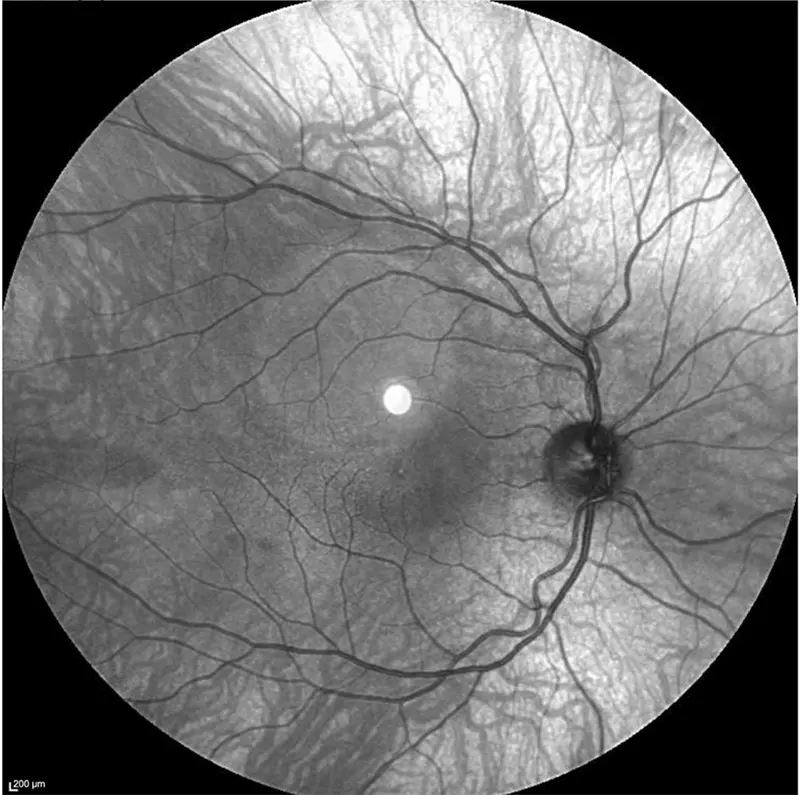

Advanced retinal imaging with Heidelberg OCT.

This scan helps us detect early signs of eye disease before vision is affected.